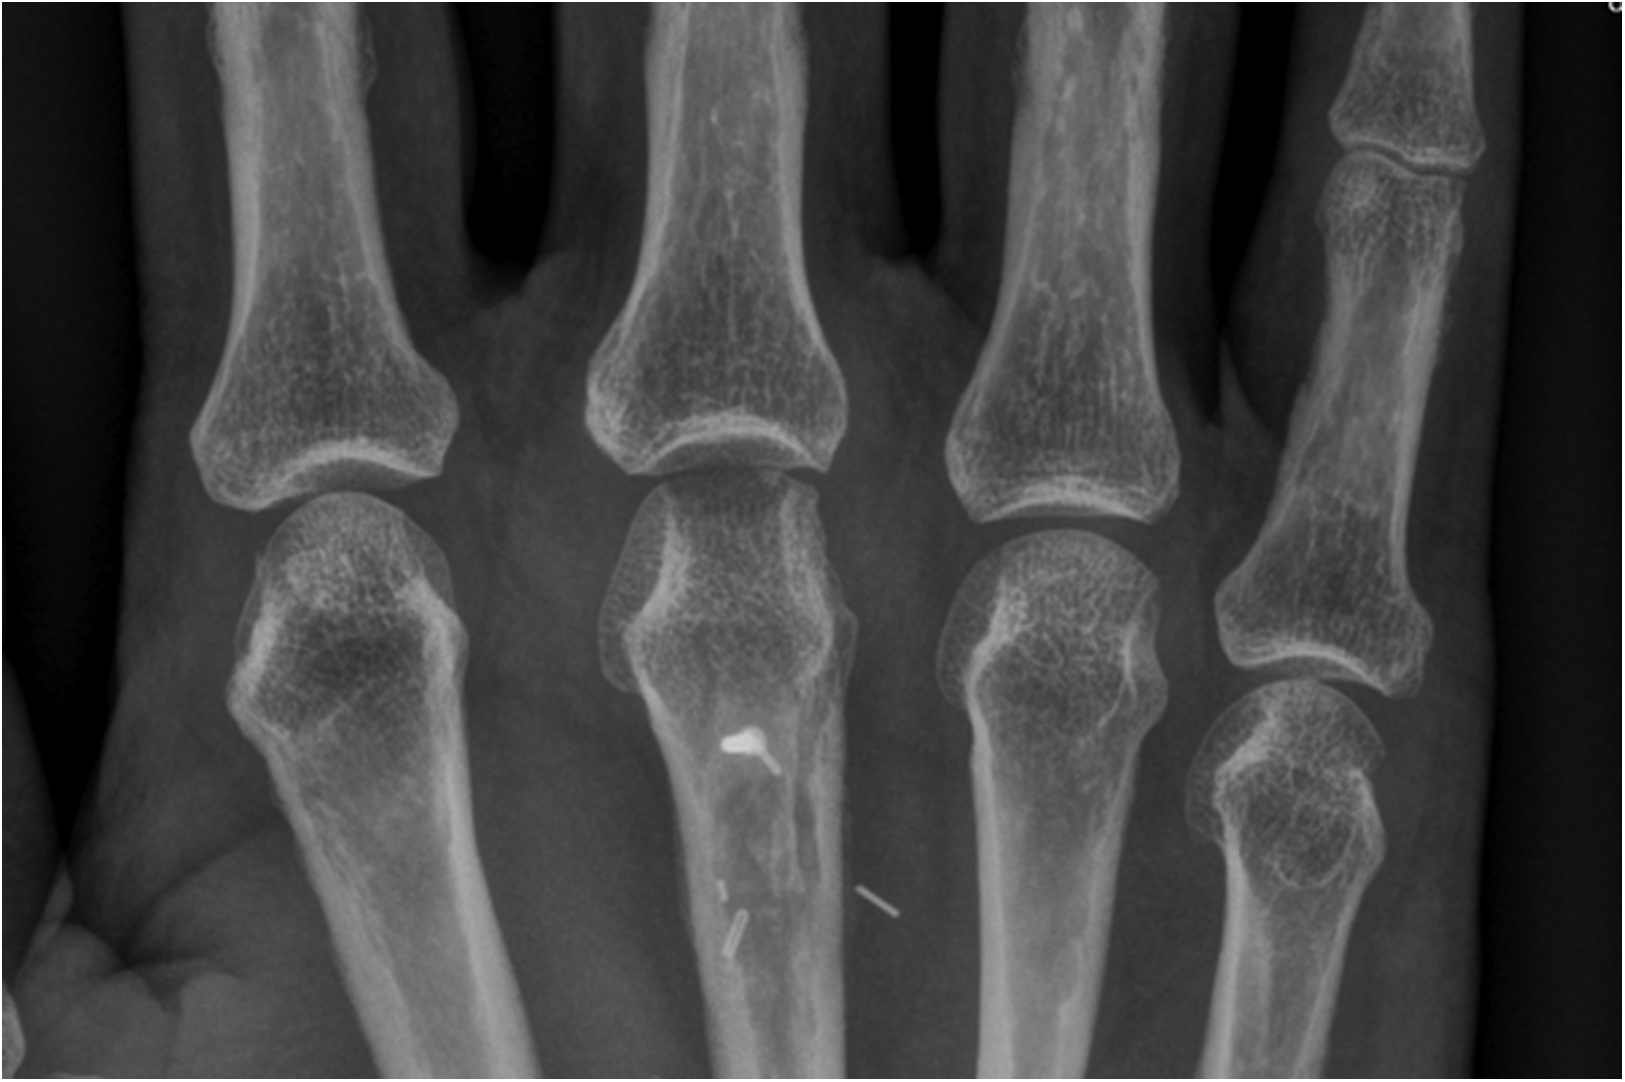

In our third case a 23-year-old male sustained a dorsal impression fracture of the third metacarpal head when attempting to strike a boxing ball in a festival machine (Figure 8). Due to his young age and physically demanding job on a building site, the patients’ main concern was pain and future osteoarthritis. Initial treatment was non-operative, with a subsequent improvement in active range of motion as swelling subsided. However, a painful clicking sensation emerged during joint movement. MRI confirmed intact base cartilage of the proximal phalanx. Considering these findings, a decision was made to reconstruct the metacarpal head using a contralateral free vascularized costochondral graft. The defect was visualized during the operation (Figure 9), after which, the graft was anchored to the remaining metacarpal using one-and-a-half millimeter cortical screws (Figure 10), with a microsurgical anastomosis linking the lateral intercostal artery to the second dorsal intermetacarpal artery, both of similar caliber. Postoperative management included initial cast immobilization, transitioning to a relative motion splint after two weeks. During the first phase of rehabilitation, a slight clicking of the joint occurred, which also disappeared spontaneously after further mobilization under guidance of the occupational therapists. Range of motion and strength is satisfactory (Figures 11 and 12), but due to his age the patient decided to pursue further education with the goal of obtaining a less physically demanding occupation in the future.